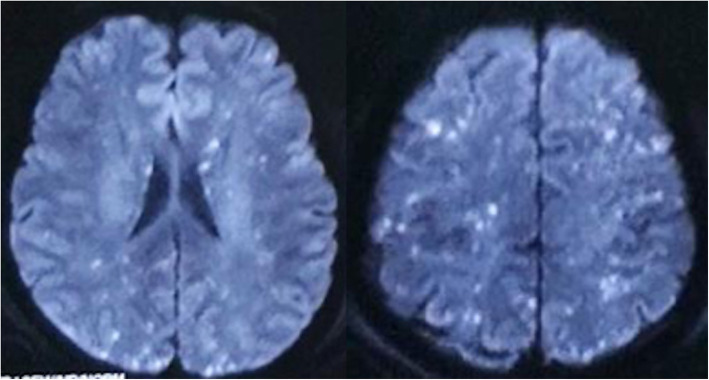

Bilateral lower extremity X-ray and pelvic CT in this patient showed multiple fractures of the bilateral lower extremities and pelvis. Head MRI showed multiple small lesions in the whole brain consistent with a “star field” pattern (Fig. 1), including high signals on T2-weighted (T2w) and fluid-attenuated inversion recovery (FLAIR) images in the bilateral centrum semiovale; both frontal, parietal and occipital lobes; and brainstem, cerebellar hemisphere, and deep and subcortical white matter. Head MRI was re-examined 15 days after admission to our hospital and revealed that the signals of these lesions on T2w and FLAIR images were slightly decreased (Fig. 2). Continuous electroencephalogram (EEG) monitoring showed generalized slow waves without epileptiform discharges. Bedside transthoracic echocardiography of this patient was highly suspicious of a patent foramen ovale. However, the transesophageal echocardiogram with bubble study failed to demonstrate an intracardiac defect or arteriovenous malformation (AVM) in the lung, further supporting a biochemical process.

Fig. 1.

Head MRI in the local emergency centre showed whole brain multiple small lesions consistent with “star field” pattern